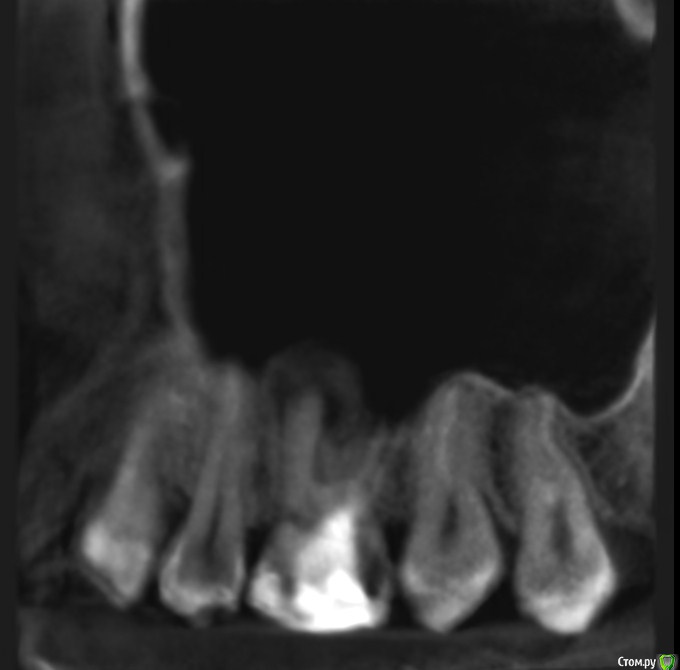

Подскажите, пожалуйста, точно удалять? Как принять это решение, все таки надежда на какой то другой лечебный вариант теплится =)post-59509-0-08196600-1578493080_thumb.jpgpost-59509-0-63211400-1578493088_thumb.jpgpost-59509-0-77705800-1578493096_thumb.jpgpost-59509-0-02698500-1578493106_thumb.jpgpost-59509-0-04880900-1578493120_thumb.jpgpost-59509-0-11411000-1578493128_thumb.jpg

По представленным срезам создаётся впечатление, что лечение вполне возможно